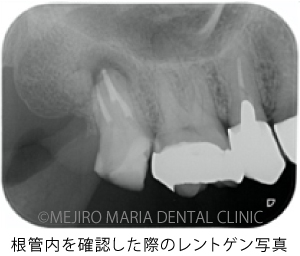

精密根管治療の開始後、根管内充填物(感染物)を除去して根管内を確認すると、歯根破折が見られました(中央写真の赤矢印)。歯根破折は根管内に留まっていましたが、歯周ポケットと繋がっていたため、1回目の治療を中止しました。

術中に歯牙を保存できる可能性がいくつか確認できたので、患者様には「①抜歯をする」 「②治療を継続し歯牙の保存にチャレンジする」、の2つの選択肢について説明させていただきました。結果、患者様は②の治療を継続し歯牙の保存にチャレンジすることを希望されました。